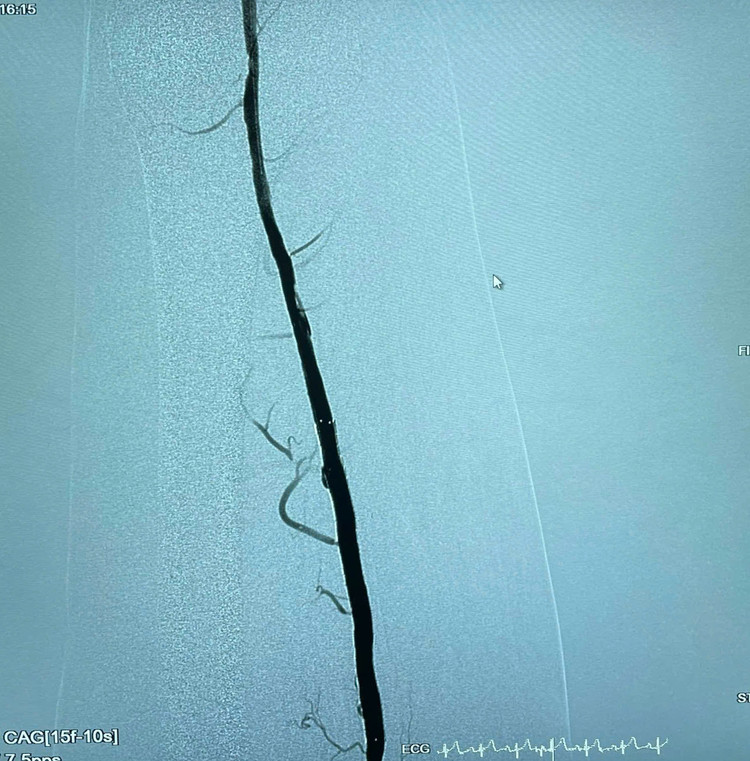

Kết quả chụp cắt lớp động mạch chi dưới cho thấy người bệnh bị tắc động mạch đùi nông chân trái, cấp máu bàn chân trái giảm nặng. Các bác sĩ đã tiến hành chụp mạch số hóa xóa nền (chụp mạch DSA) để xác định vị trí và mức độ tổn thương tắc động mạch đùi nông, ngay sau đó người bệnh đã được nong bóng và đặt stent tại vị trí hẹp tắc.

Kết quả chụp kiểm tra sau can thiệp cho thấy động mạch đùi nông đã được tái thông hoàn toàn, cấp máu cho bàn chân trái tốt, tình trạng người bệnh được cải thiện chân trái giảm phù nề, đỡ đau nhức.

| Động mạch của người bệnh bị tắc trước can thiệp (vị trí mũi tên chỉ) và sau can thiệp - Ảnh BVCC |